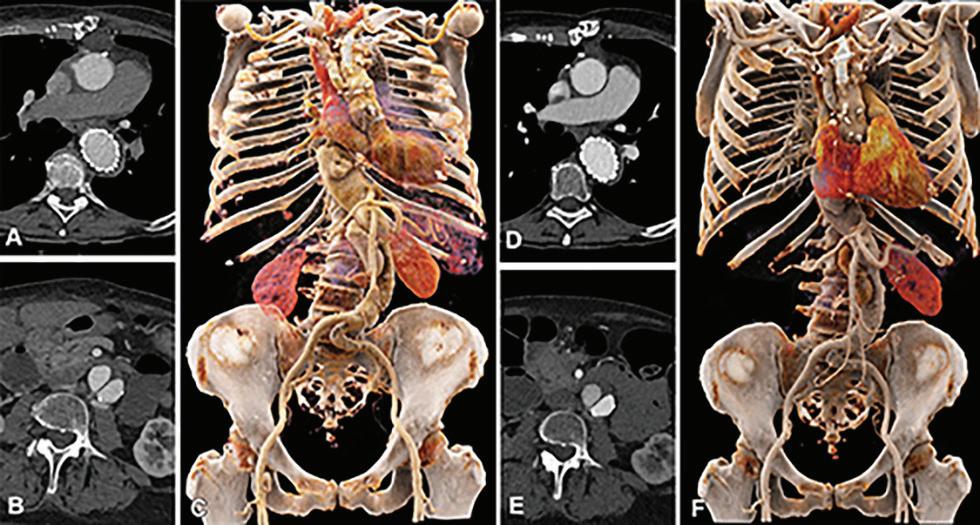

EID CT y PCD CT utilizando un protocolo de medio de contraste idéntico y una dosis de radiación equivalente. Las imágenes transversales de CTA muestran la aorta torácica al nivel del tronco pulmonar en un hombre de 62 años en el grupo 1, que se muestra utilizando configuraciones de ventana idénticas (centro de ventana: 350 HU, ancho de ventana: 1000 HU). (A) Imágenes de exploraciones realizadas con un sistema CT de fuente dual de tercera generación con EID. (B–F) Imágenes de PCD CT con VMI a niveles de energía de 40 a 60 keV. El intervalo de tiempo entre las exploraciones fue de 11 meses. Ambos escaneos se realizaron con el mismo protocolo de medios de contraste (volumen, 70 ml). Tenga en cuenta la mayor atenuación del vaso a niveles de energía más bajos para PCD CT. CTA = angiografía por TC, EID = detector de integración de energía, PCD = detector de conteo de fotones, VMI = imágenes monoenergéticas virtuales.

Figura 5. Comparación de la calidad de imagen entre EID CT con protocolo de medios de contraste estándar y PCD CT con protocolo de medios de contraste de bajo volumen utilizando una dosis de radiación equivalente. Se muestran imágenes renderizadas cinemáticas transversales y tridimensionales de la ATC toracoabdominal en una mujer de 71 años del grupo 2. (A–C) Imágenes de EID CT de tercera generación con selección automática de voltaje de tubo de 90 kVp. (D-F) Imágenes de PCD CT con volumen de medio de contraste reducido de 52,5 ml y VMI a 50 keV. El intervalo de tiempo entre las exploraciones fue de 6 meses. CTA = angiografía por TC, EID = detector de integración de energía, PCD = detector de conteo de fotones, VMI = imágenes monoenergéticas virtuales.